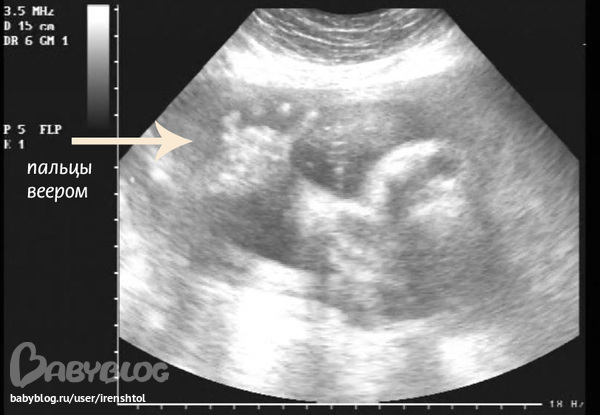

Записали видео, но малышок уже большой и видно только отдельные части тела ) Вырезала стоп-кадр :)

Вот такая у нас "задняя" лапка с пальчиками :)) мизинчик прижат, так мило :)